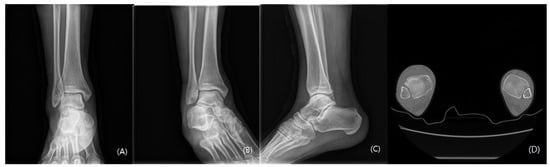

2. Case Presentation